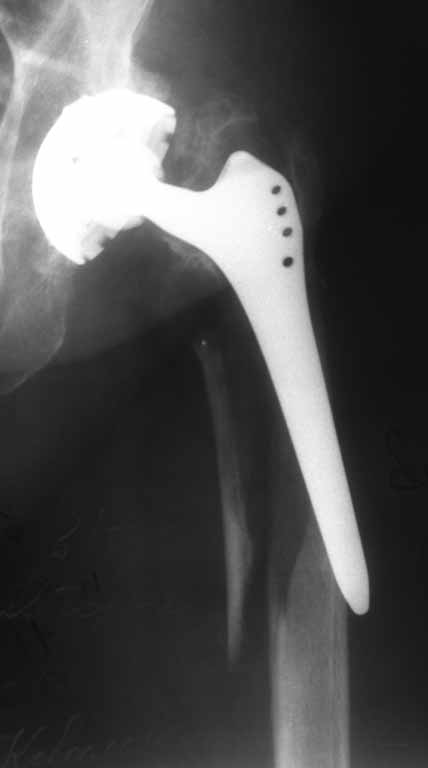

Перипротезный перелом бедра

Пациентка 86 лет. Травма в результате падения.

планируется замена ножки на ревизионную + серкляжи на отломки. Может что нибудь еще?

Мы бы использовали подход, который уже на форуме был представлен, см., например, тут. Пациентка в почтенном возрасте, малоинвазивное удлинение ножки, закрыто, без кровопотери, наверно, тут предпочтительней формальной ревизии.